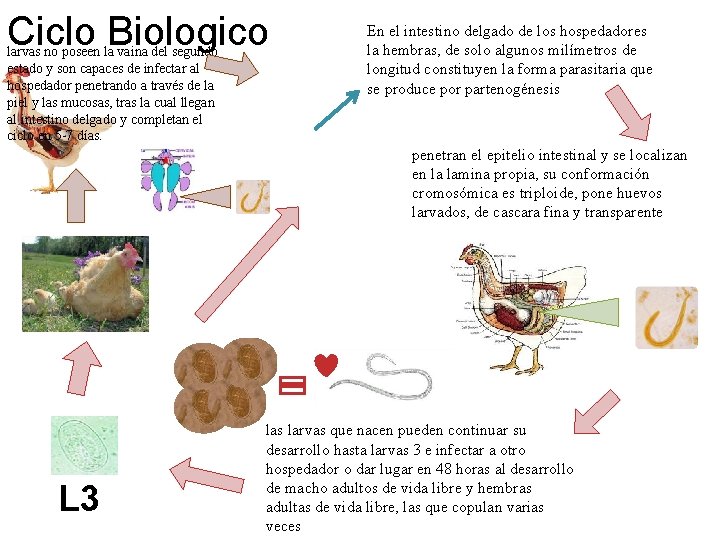

Ciclo Biologico larvas no poseen la vaina del segundo estado y son capaces de infectar al hospedador penetrando a través de la piel y las mucosas, tras la cual llegan al intestino delgado y completan el ciclo en 5 -7 días. En el intestino delgado de los hospedadores la hembras, de solo algunos milímetros de longitud constituyen la forma parasitaria que se produce por partenogénesis penetran el epitelio intestinal y se localizan en la lamina propia, su conformación cromosómica es triploide, pone huevos larvados, de cascara fina y transparente L 3 las larvas que nacen pueden continuar su desarrollo hasta larvas 3 e infectar a otro hospedador o dar lugar en 48 horas al desarrollo de macho adultos de vida libre y hembras adultas de vida libre, las que copulan varias veces